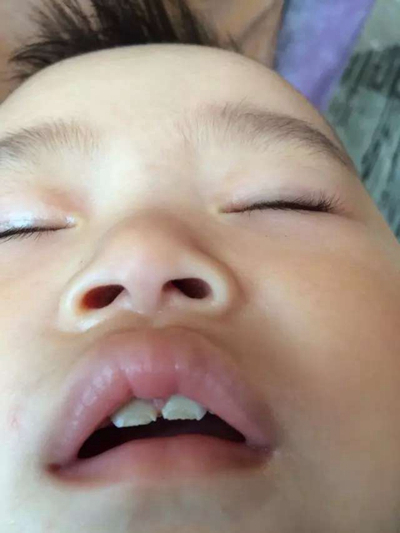

齲齒圖片

蟲牙真實

蟲牙真實

蟲牙真實

蟲牙真實

蟲牙真實

蟲牙真實

蟲牙真實

蟲牙真實

蟲牙真實

蟲牙真實

蟲牙真實

蟲牙真實

蟲牙真實

蟲牙真實

蟲牙真實

蟲牙真實

蟲牙真實

蟲牙真實

蟲牙真實

蟲牙真實